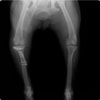

6歳 Mix犬 3.5kg

[主訴]

散歩で駆け出した後にキャンと鳴いてから右後肢を挙上しているとのことで来院。

[検査]

触診検査 MPL左右GradeⅡ

レントゲン検査 にて

右脛骨前方変位あり、ファットパッドサインあり

脛骨公平部角(TPA)の急峻を認める

[治療]

検査結果から前十字靱帯の断裂を疑い脛骨高平部水平化骨切り術(TPLO)を実施することに。また、パテラの安定化のために縫工筋内側広筋切開、滑車溝形成術も併せて実施。

手術前TPA 28.4° が術後TPA 11.7° に矯正されました。